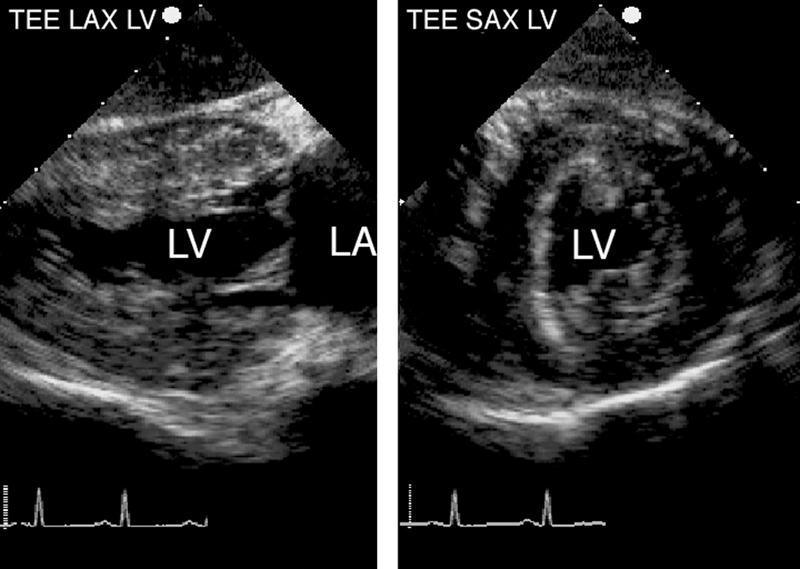

فحوصات تشخيصية لبعض امراض القلب والشرايين التاجية